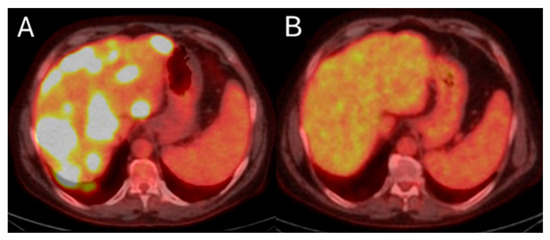

Metabolic response by FDG-PET/CT usually precedes imaging response by ceCT and ceMRI. Metabolic response of CLM can be detected as soon as 4 to 6 weeks after treatment [20,180]. Demonstrating response early can be crucial for patients requiring bilobar radioembolization. Confirming disease response to 90Y justifies utilization of the treatment strategy to the contralateral hepatic lobe (Figure 8). On the contrary, in cases with lack of metabolic response or progression within the treated hepatic area, alternative treatments can be proposed. Continuous disease monitoring is recommended thereafter every 2–4 months for at least 1 year [172,181].

Figure 8.

55-year-old male with history of colorectal adenocarcinoma currently on systemic chemotherapy undergoes trans-arterial radioembolization with Ytrium-99 microspheres for multifocal liver dominant metastatic progressive chemorefractory disease in salvage settings. Pre-procedure FDG-PET/CT indicates diffuse bilobar disease (A). The eight months post-initial TARE demonstrates sustained disease control while the patient is under chemotherapeutic coverage (B).